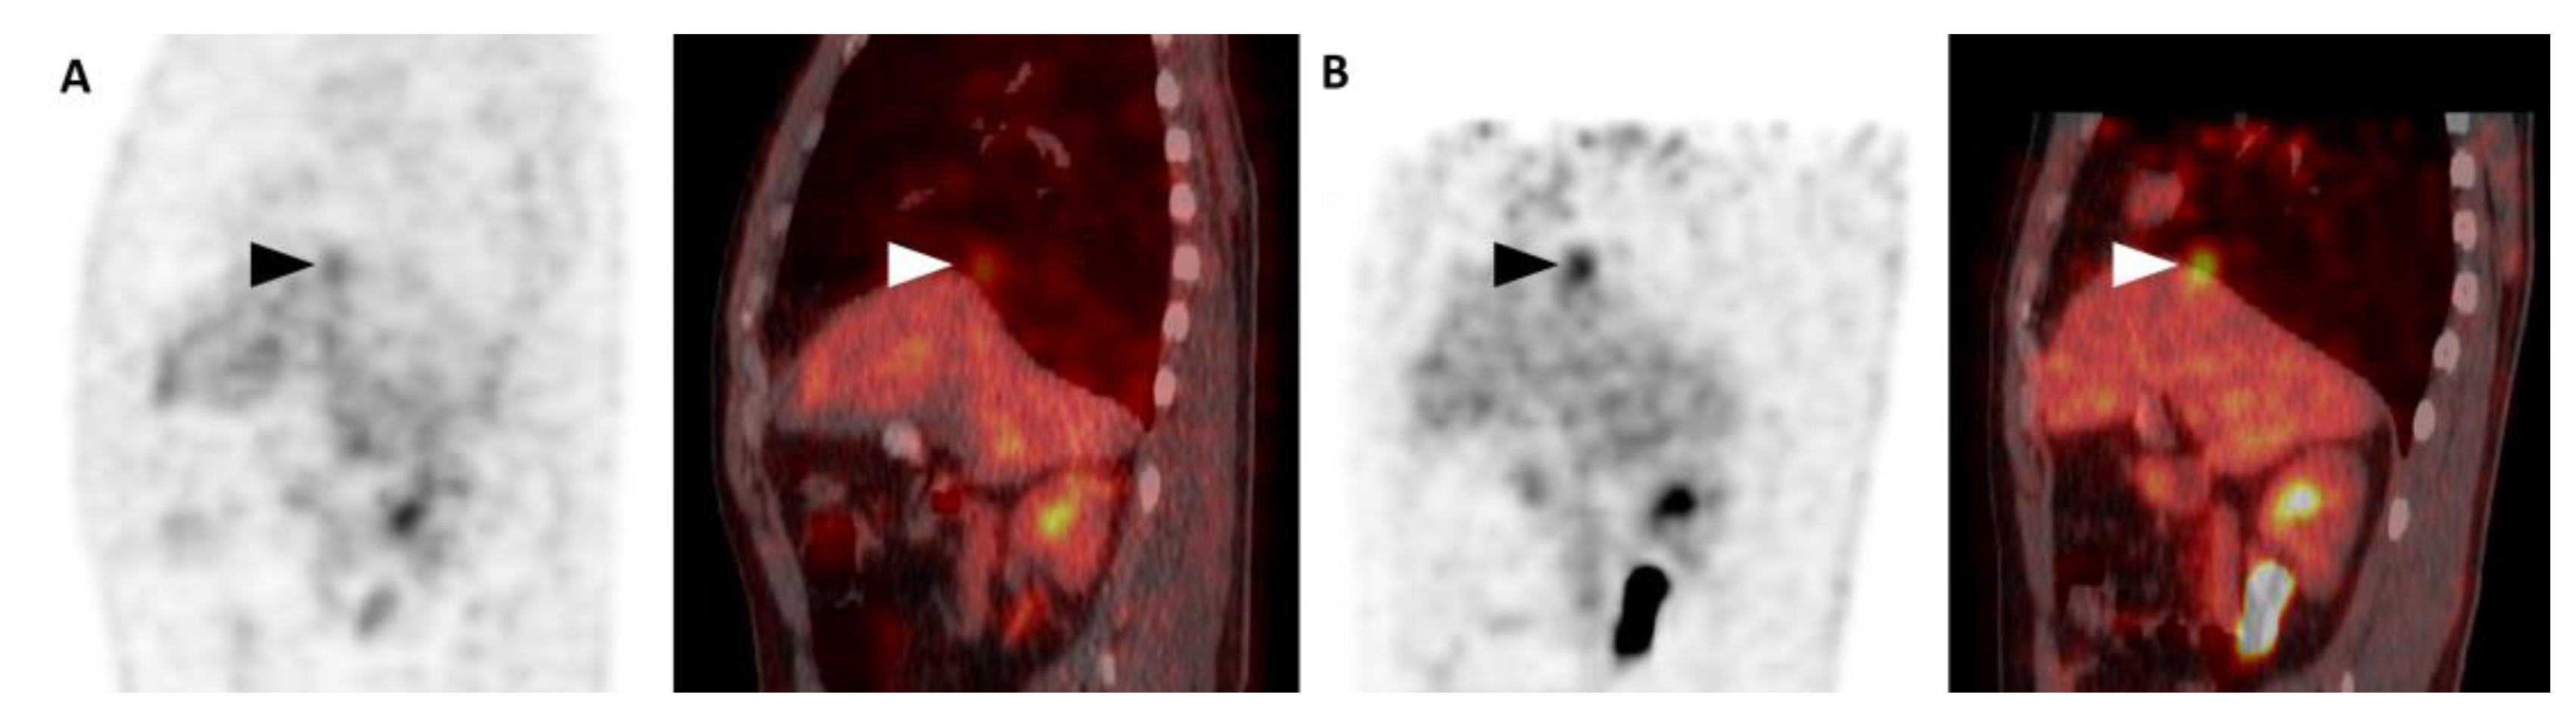

3. Results

4. Discussion

| Reasons | Change of SUVmax (%) | n (%) | |

|---|---|---|---|

| Median | Range | ||

| [18F]FDG uptake outside the liver on CT in sPET/CT | 15% | [7% to 71%] | 4 (11%) |

| More blurring in sPET/CT | 11% | [−3% to 32%] | 6 (17%) |

| Unremarkable | 1% | [−8% to 18%] | 12 (34%) |

| More blurring in pPET/CT | −19% | [−30% to −8%] | 12 (34%) |

| [18F]FDG uptake outside the liver on CT in pPET/CT | −30% | [−30% to −30%] | 1 (3%) |

| Total patients | −4% | [−30% to 71%] | 35 (100%) |